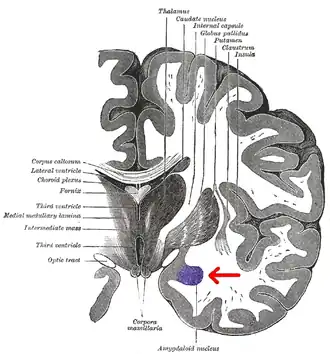

Миндалевидное тело (лат. corpus amygdaloideum), ами́гдала[1] — область мозга миндалевидной формы, находящаяся в белом веществе височной доли полушария под скорлупой, примерно на 1,5—2,0 см сзади от височного полюса. В мозге два миндалевидных тела — по одному в каждом полушарии[2]. Миндалевидное тело играет ключевую роль в формировании эмоций, в частности, страха. У пациента, миндалевидное тело которого оказалось полностью разрушено вследствие болезни Урбаха — Вите, наблюдалось отсутствие страха[3][4][5]. Миндалевидное тело также играет важную роль в функционировании памяти, принятии решений и эмоциональных реакциях[6]. Миндалевидное тело является частью лимбической системы, относится к подкорковым обонятельным центрам.

Области мозга, называемые миндалевидными ядрами, включают несколько структур со схожими функциональными характеристиками у человека и животных[7]. В число этих структур входит базолатеральный комплекс, ядра коры, срединное ядро, центральное ядро и клетки интерстиция. Базолатеральный комплекс, в свою очередь, делится на латеральное, базальное и добавочное ядра[6][8][9]. Анатомически миндалевидное тело[10], в частности, его центральное и медиальное ядра[11], иногда включаются в состав базальных ганглиев.

Миндалевидное тело посылает импульсы в гипоталамус, дорсомедиальный таламус, ретикулярное таламическое ядро, ядра тройничного и лицевого нервов, вентральной области покрышки, голубого пятна и дорсолатерального ядра покрышки[8]. Медиальное ядро вовлекается в процесс обоняния и восприятия феромонов. Оно получает информацию от обонятельной луковицы и обонятельной коры[23]. Латеральное ядро, которое посылает импульсы базолатеральному комплексу и центромедиальному ядру, получает информацию от органов чувств. Эти структуры также задействованы в возникновении эмоций у крыс и кошек[8][9][24].